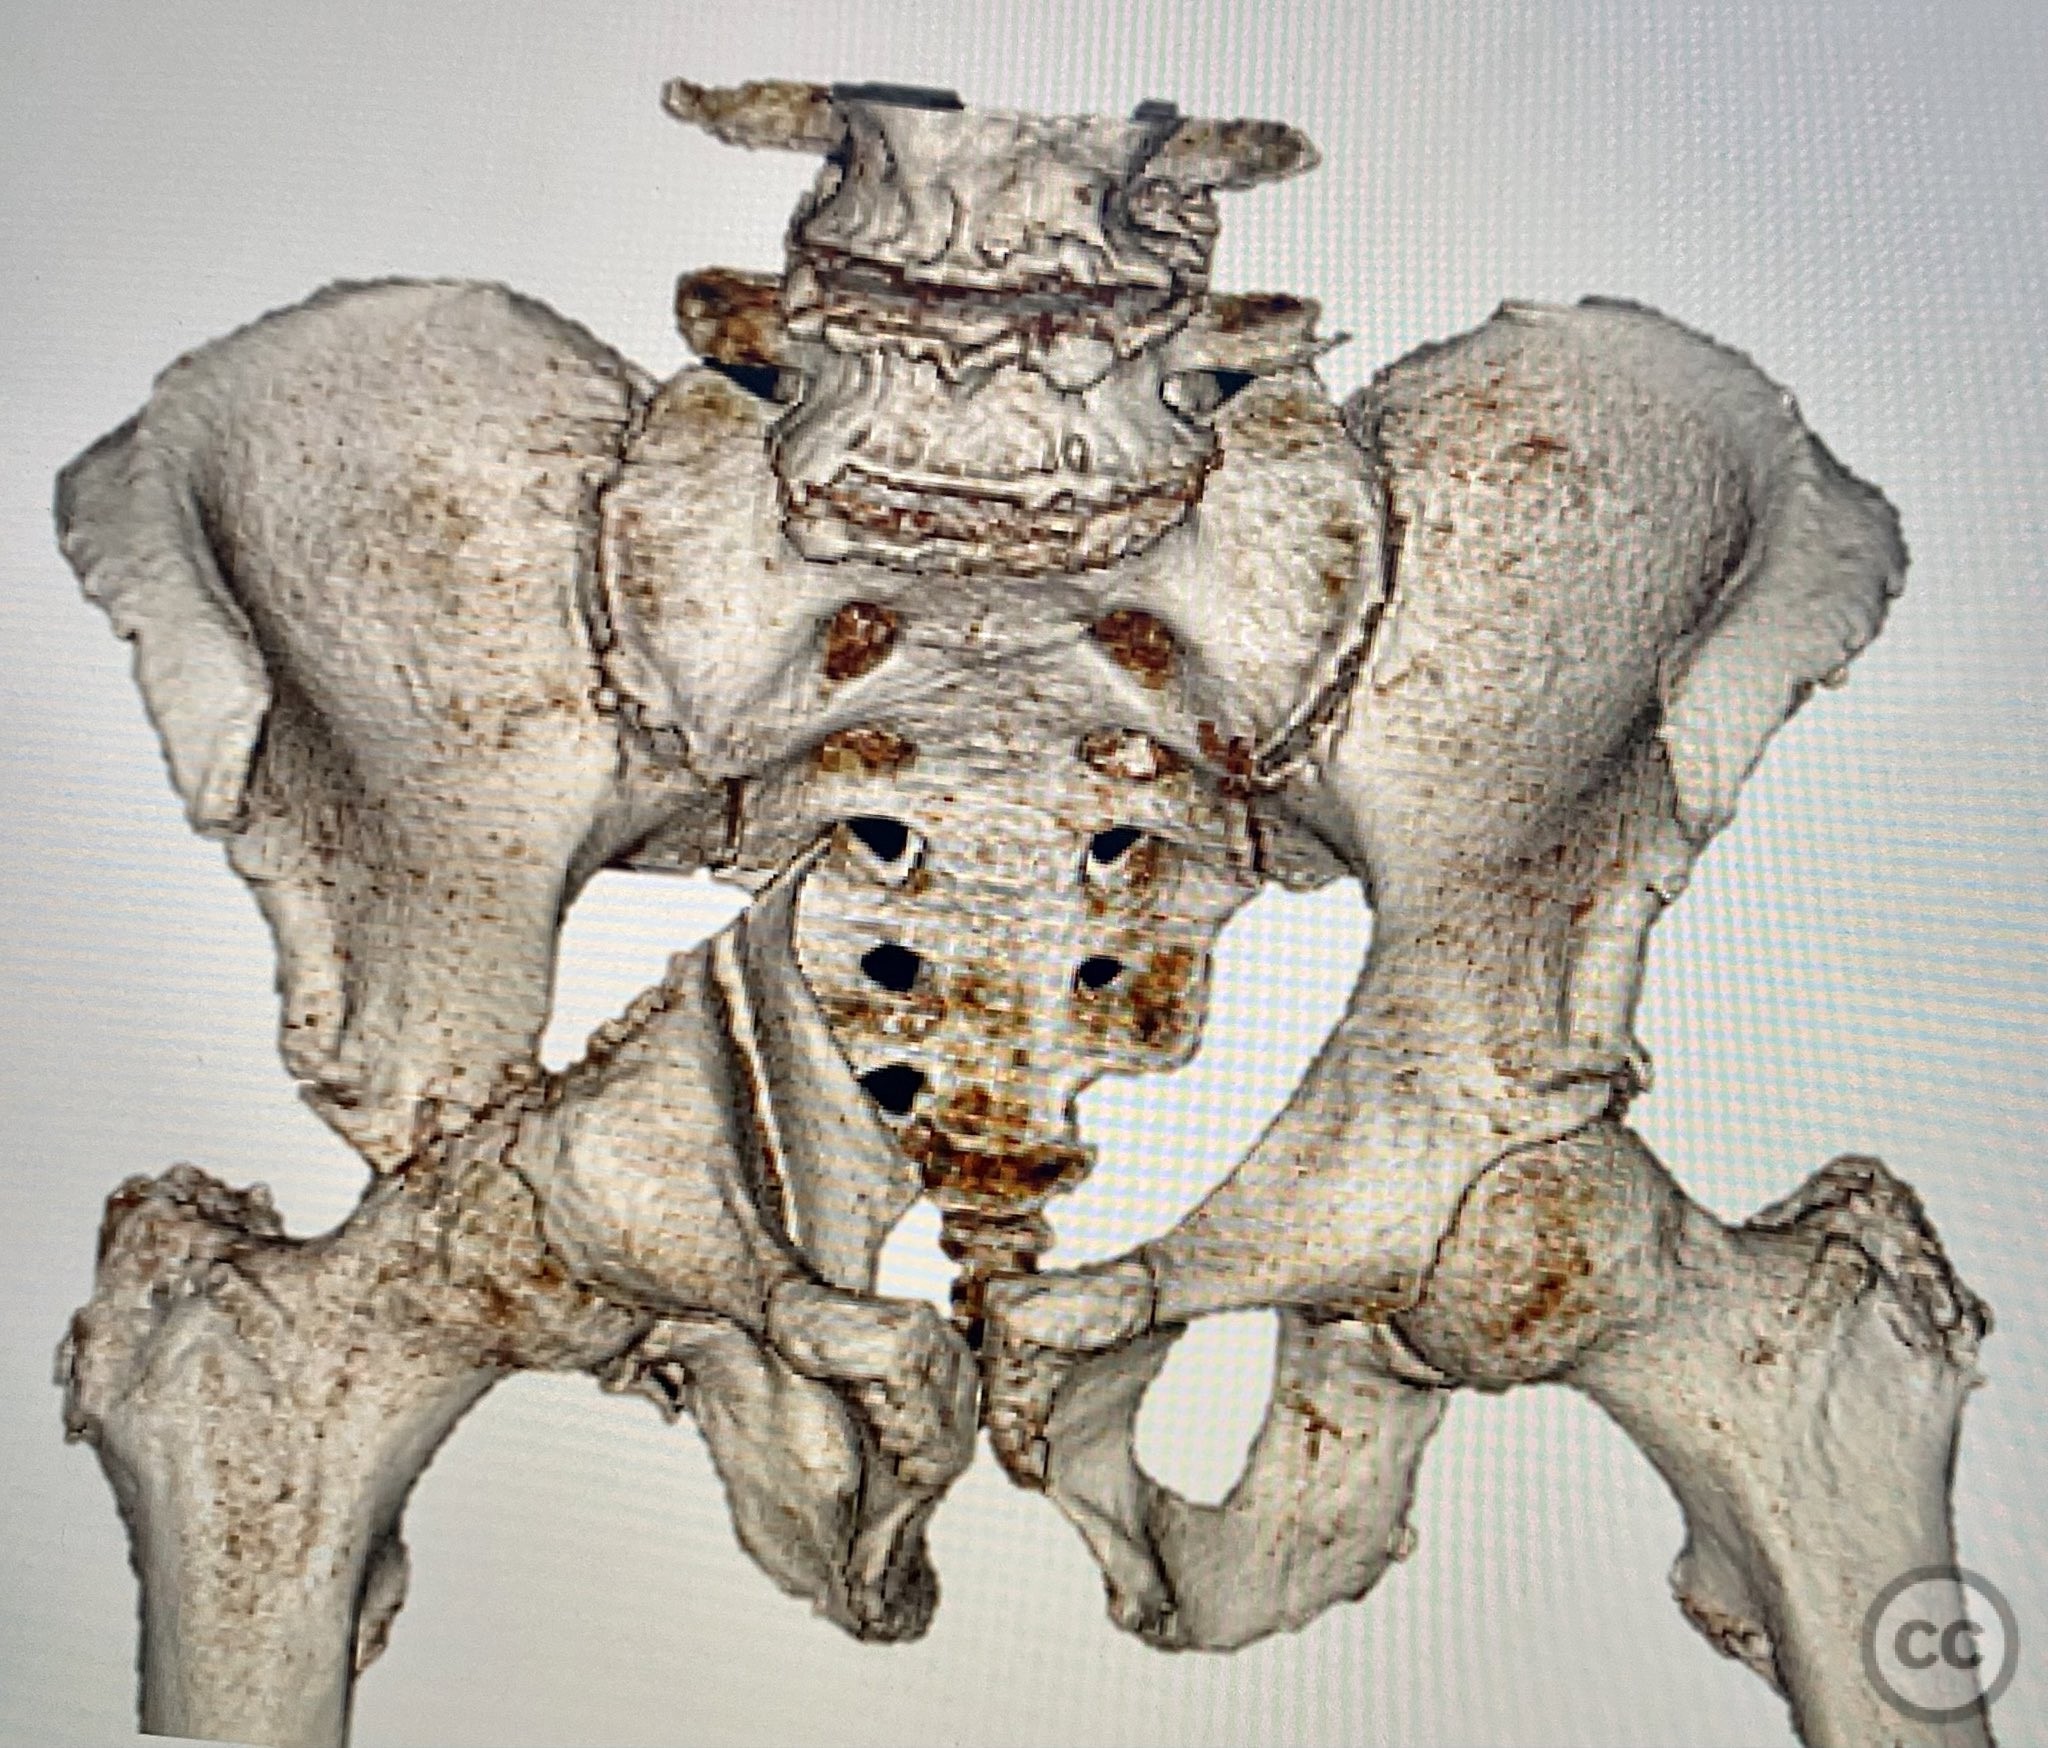

Clinical and radiological findings:  A 79-year-old male sustained a high-energy injury in a motor vehicle collision, resulting in a complex acetabular fracture-dislocation. Radiographs and computed tomography demonstrated a posterior wall and transverse acetabular fracture (AO/OTA 62-B1.3), with the posterior wall fragments displaying an atypical caudal hinge configuration. The medial wall fragment was non-articular. Axial imaging revealed an impacted osteochondral fragment obstructing reduction, as well as disruption of the capsular structures adjacent to the intact articular segment. The obturator internus tendon appeared taut but intact, with no evidence of sciatic nerve impingement or superior gluteal neurovascular compromise.

Planning remarks:  The preoperative plan included open reduction and internal fixation via a Kocher-Langenbeck approach in the prone position. The strategy entailed removal of the impacted intra-articular fragment, anatomic reduction and provisional fixation of the transverse component, reduction and fixation of the posterior wall, bone grafting and reduction of the impacted articular segment via the medial wall window, and definitive fixation of the medial wall. Capsular repair was planned prior to closure.